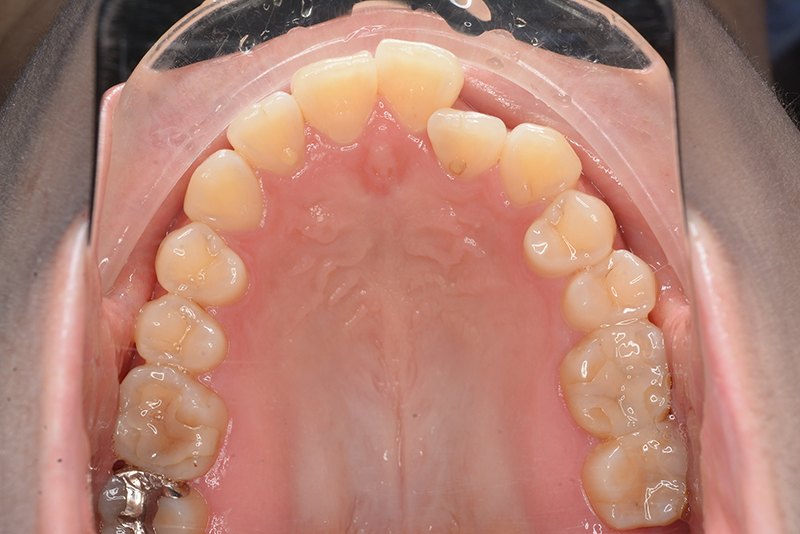

| 口腔内所見 | 臼歯関係はⅠ級、over jet 4.5mm、over bite -3.0mm。上下顎切歯部に軽度の叢生が認められ唇側傾斜をしつつ開咬を呈していた。 |

| セファロ所見 | Sellaから下顎頭までの距離は短く、骨体部は大きいが下顎枝の長さが短く、下顎角は開大しているためハイアングルを呈していた。中顔面部の高さは高いため下顎はクロックワイズローテーションをしており前後的にはII級の骨格形態を示していた。 |

| 批評・予后 | 治療後において下顎角の開大も認められず歯軸の整直、咬合の緊密化が得られた。また上下顎前歯の後退と共に口元の突出感と口唇閉鎖不全の改善が認められた。 |